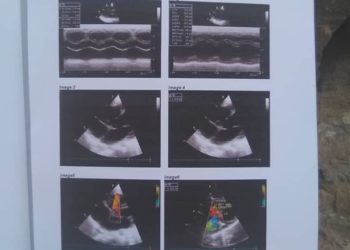

كتب / محمد العزعزي الطفلة افنان رياض ياسين عبدالله الزريقي تبلغ من العمر عامين تسكن التربة بالشمايتين في تعز وهي...